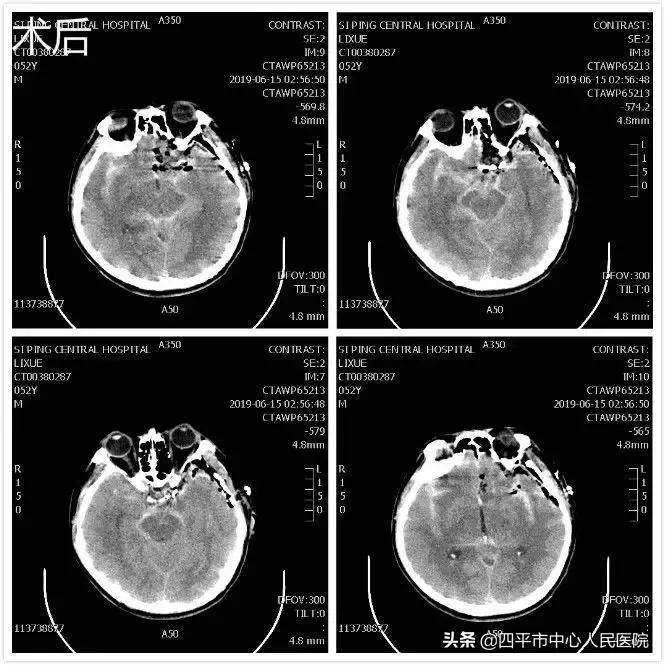

患者刘XX,缘于入院前2小时无明显诱因在劳动时突发意识不清,从2米高处坠落,既往身体健康,入院头部CT提示蛛网膜下腔出血,李晓东主任阅头部CT片后指示该患者应该是先脑出血而后摔倒,不能除外动脉瘤破裂,入院后完善头部CTA检查,提示1.左侧颈内动脉末端动脉瘤。2.左侧大脑中动脉闭塞。3.双侧颈内动脉颅内段轻度狭窄。4.脑内动脉粥样硬化改变。5.右侧胚胎型大脑后动脉。李晓东主任带领孙庆华急诊全麻下行左侧颈内动脉末端动脉瘤夹闭术,术中注意避免误夹后交通动脉,否则造成的后果是灾难性的,经术中仔细操作,确切夹闭动脉瘤,术中顺利,术后患者病情逐渐好转,出院时神清语明,四肢肌力5级,送来锦旗表示感谢。